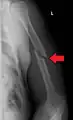

| Midshaft humerus fracture with callus formation | |

A transverse fracture of the humerus shaft